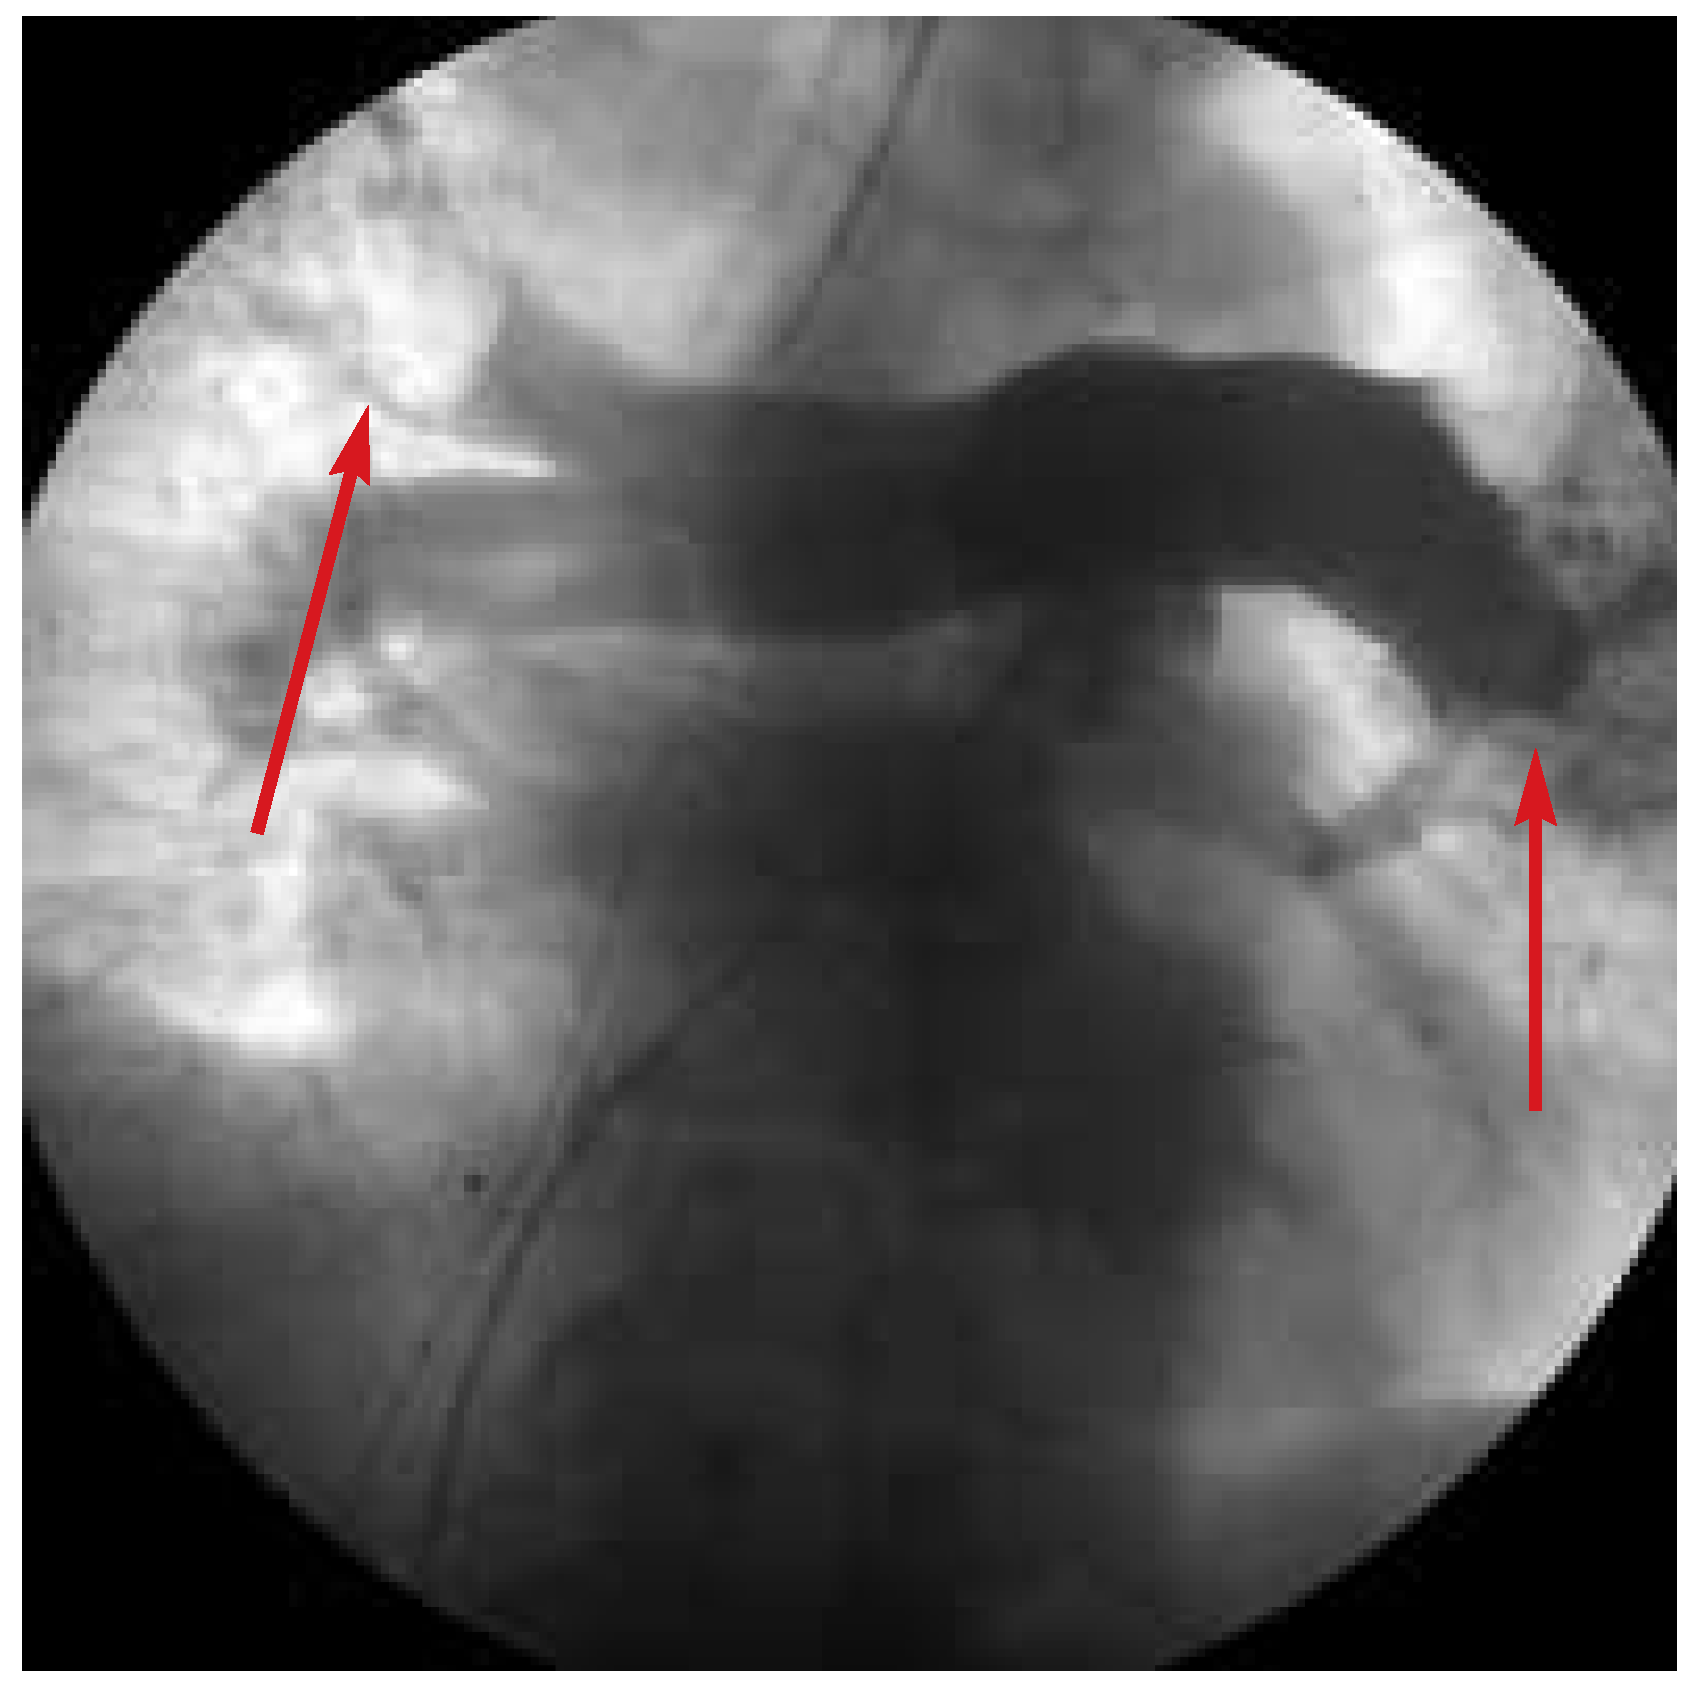

Abbildung 3. Partielle Rekanalisierung der oberen rechten Lungenarterie durch Katheterfragmentierung. Es können nun vorher nicht sichtbare Gefässe dargestellt werden (Markierung).

Ein 60jähriger Mann ohne bekannte kardiovaskuläre Risikofaktoren stellte sich mit seit einigen Wochen zunehmender Dyspnoe in der Notaufnahme vor. Schon bei Spitaleintritt waren die Kriterien eines kardiogenen Schocks erfüllt: Der systemische Blutdruck betrug 80/60 mm Hg, die Herzfrequenz 110/min, auffällig waren zudem massiv gestaute Halsvenen. Aufgrund des Rechtsschenkelblockbildes im EKG mit S1—Q3-Phänomen (Abb. 1) sowie einer massiven Dilatation der rechten Herzkammern in der Echokardiographie stellten wir die Verdachtsdiagnose einer zentralen, lebensbedrohlichen Lungenembolie und leiteten eine systemische Fibrinolyse mit r-tPA (front loaded) ein. Leider führte diese Massnahme nicht zu einer klinischen bzw. hämodynamischen Besserung des mittlerweile kritischen Zustands des Patienten, so dass rasch ein chirurgischer Eingriff bzw. eine mechanische Desobstruktion der Lungenzirkulation in Erwägung gezogen werden musste. Da die Herz-Lungen-Maschine wegen einer gleichzei-tig stattfindenden Bypass-Operation nicht zur Verfügung stand, entschieden wir uns für eine mechanische, endoluminale Fragmentierung und damit Mobilisierung des thrombotischen Materials. Zwischenzeitlich machten zunehmende, therapierefraktäre Bradykardien die Einlage eines provisorischen Herzschrittmachers notwendig. Schliesslich zeigte die nicht selektive Pulmonalis-Angiographie (Abb. 2) eine fast vollständige Amputation beider pulmonal-arterieller Gefässstämme. Mit verschiedenen Kathetern versuchten wir die ausgeprägten thrombotischen Ablagerungen zu zerkleinern und damit zu mobilisieren, allerdings nur mit partiellem Erfolg (Abb. 3). Der Patient verstarb schliesslich nach einer prolongierten Reanimation in Folge einer elektromechanischen Entkopplung.